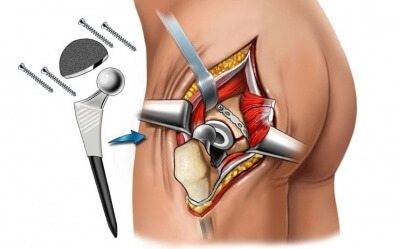

Эндопротезы тазобедреного сустава